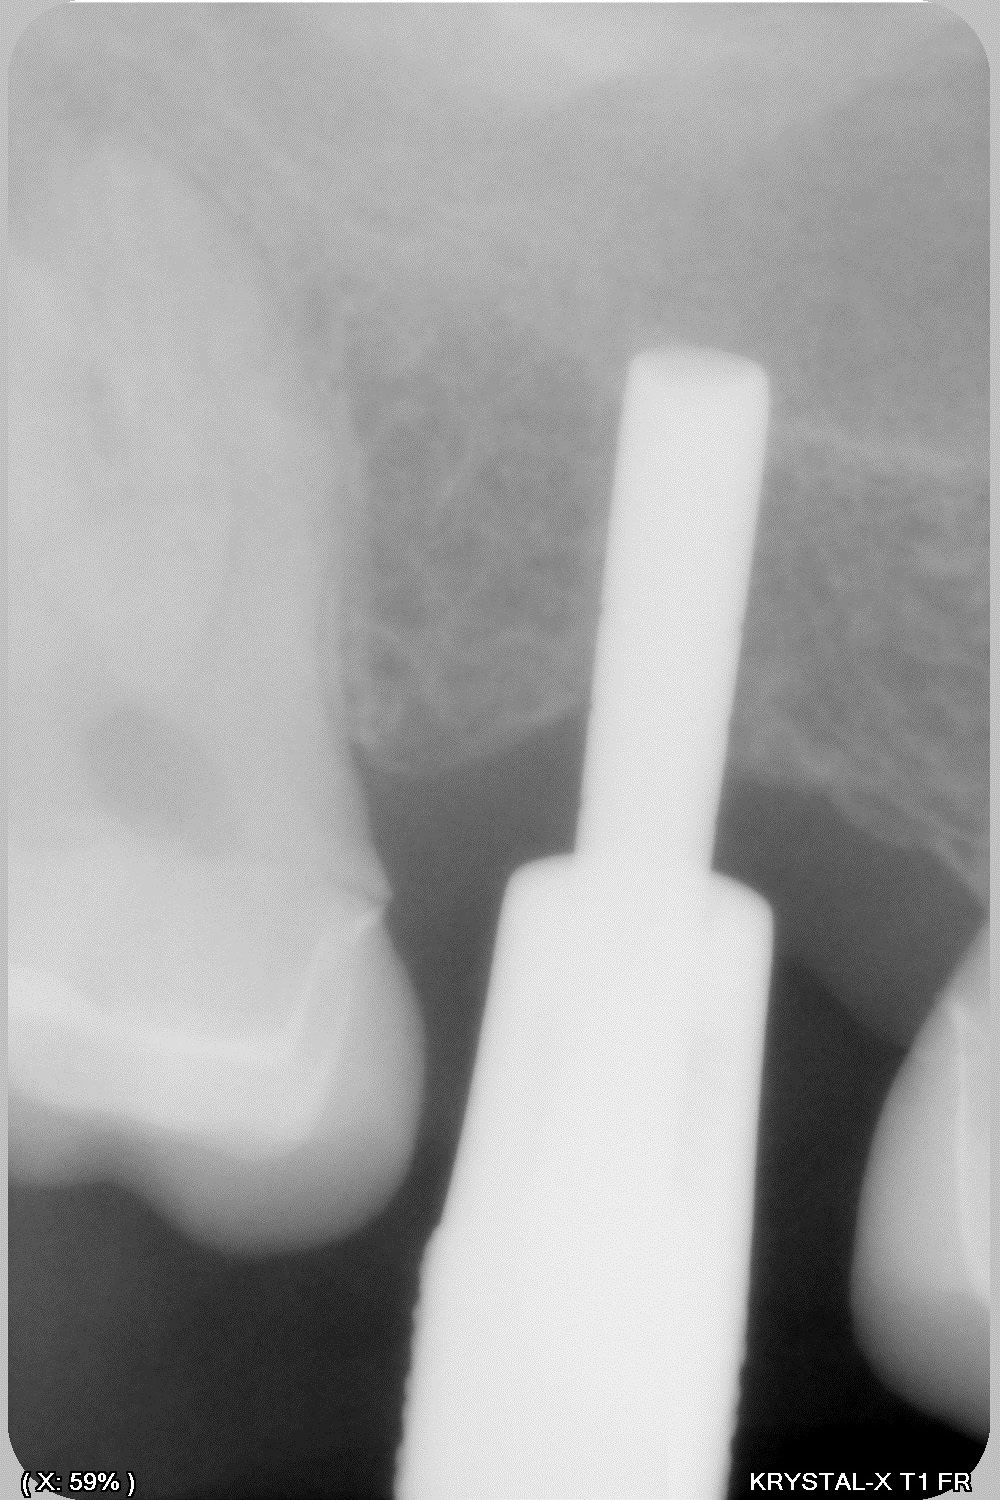

14/01/2020 à 13h00

donc tu avais raison Enlaye... le bridge à cassé (sur un carambar quand même:-))

dépose, nettoyage sablage des couronnes récupérable et pose d' implant, uniquement en manuel (os tendre)